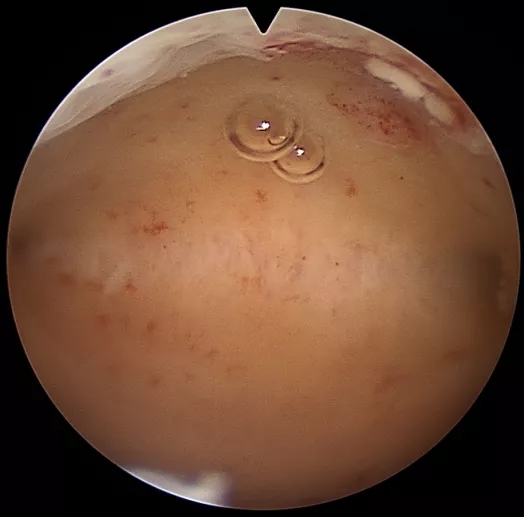

宫腹腔镜后

在牡丹妇产医院,张女士被确诊为子宫腺肌病+II型糖尿病+贫血。考虑到张女士无生育需求,多种保守治疗方案效果不佳。将其血糖调整平稳,纠正其贫血后,杨东琴主任为其实施了腹腔镜下全子官切除加双侧输卵管切除术。

张女士子宫后壁明显增厚,子宫增大,如孕3月大小,术中空间小,子宫后壁距离肠管近,增加了手术的难度。凭借杨主任精湛的技术与团队的密切配合,手术顺利,子宫切除后由阴道取出。术后回访时,张女士对手术效果很满意。